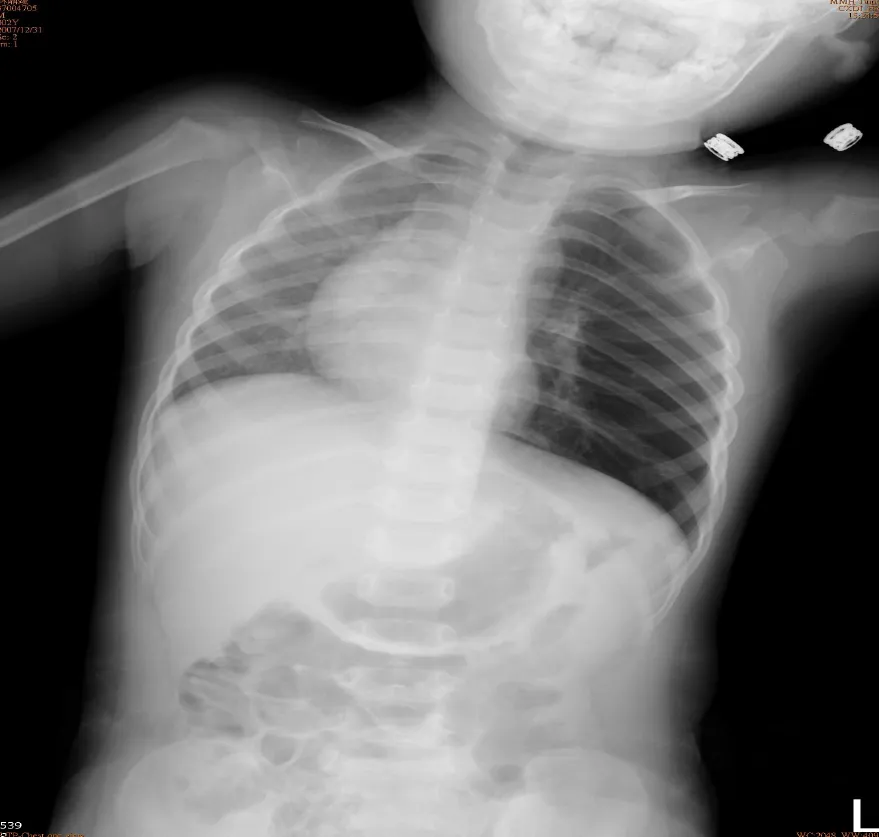

破題關鍵

這是一個典型的兒童呼吸道異物案例,影像上最關鍵的線索是左側肺部過度充氣(hyperinflation)合併縱膈腔(mediastinum)向右側偏移。

選項拆解